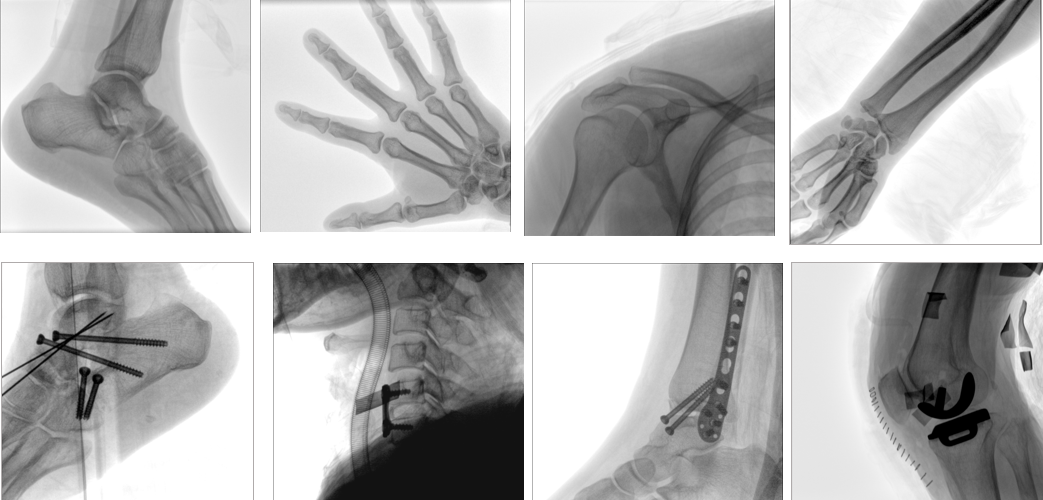

【產品臨床圖片】